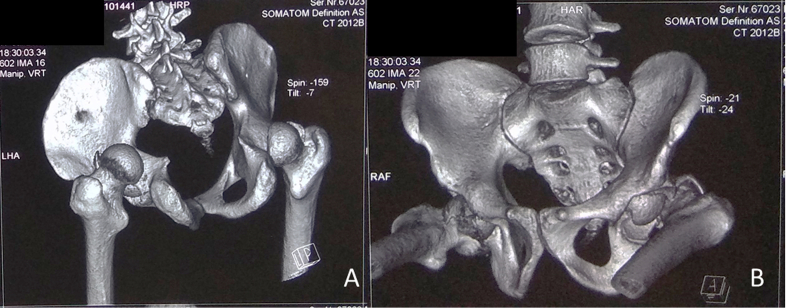

Fig. 3.

3D Reconstruction of Computed Tomographic scan show bilateral posterior hip dislocation with large femoral head fragments inside the joint.